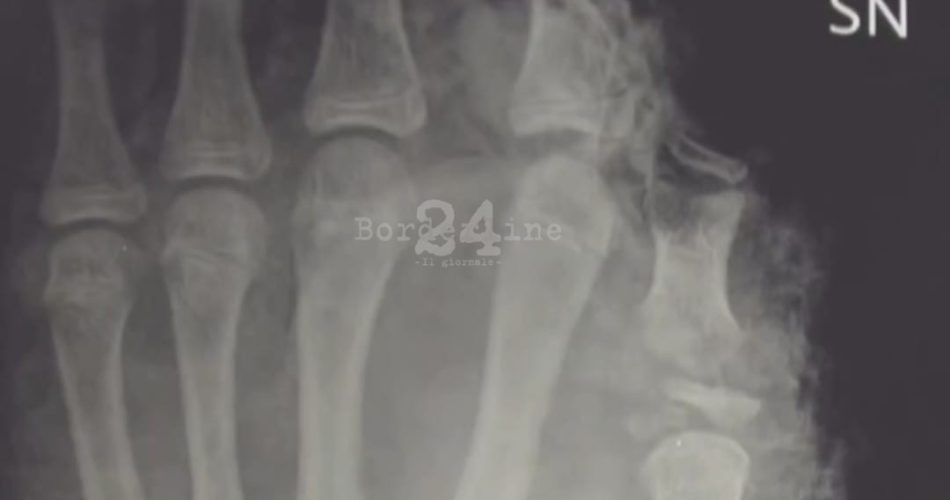

petardi fuochi mano

Già due gravi incidenti causati dallo scoppio di petardi durante le festività natalizie sono stati trattati al Policlinico di Bari, entrambi con esiti devastanti come l’amputazione di arti. Episodi che hanno spinto la direzione aziendale, in collaborazione con l’Unità operativa di chirurgia plastica e ricostruttiva, a realizzare e diffondere sulla pagina Instagram @polibari2020 un video di forte impatto per lanciare un appello in vista della notte di Capodanno. Nel video si alternano gli inviti dei medici e degli operatori sanitari alle immagini cliniche delle conseguenze provocate dai botti: amputazioni, radiografie, arti ricostruiti e mani private di dita al termine di complessi interventi di chirurgia plastica ricostruttiva. Le immagini sono accompagnate da un messaggio finale netto e inequivocabile: “Il miglior modo per proteggersi è non usarli”.

Nel trattamento di queste lesioni la chirurgia plastica e ricostruttiva riveste un ruolo centrale nell’emergenza, essendo chiamata a intervenire nella ricostruzione dei tessuti molli, nella riparazione di nervi e tendini, nella rivascolarizzazione degli arti e, nei casi più complessi, nel reimpianto delle dita amputate, spesso conseguenza dei traumi da scoppio.

“La tempestività dell’intervento e la competenza multidisciplinare — specifica la dott.ssa Eleonora Nacchiero, dirigente medico della Chirurgia Plastica — risultano decisive per salvare la funzione degli arti e degli occhi e per ridurre sequele di difficile correzione chirurgica tardiva. Tuttavia, in questi casi la missione ricostruttiva della nostra specialità non sempre può sortire gli effetti desiderati, poiché i petardi provocano una distruzione ampia e completa dei tessuti molli e ossei, rendendo talvolta inefficaci interventi complessi e di lunga durata”.